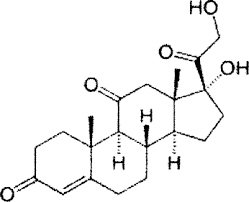

قیمت: 32٬000 تومان - دسته بندی فایل: علوم پزشکیپاورپوینت Adrenocorticosteroids

فروش ویژه پاورپوینت حرفه ای Adrenocorticosteroids با تخفیف استثنایی فقط 55 هزار تومان تعداد اسلاید: 22 اسلاید